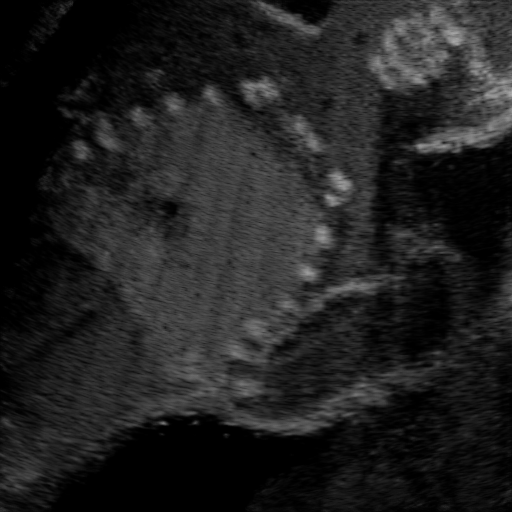

Qualitative Results. Fig. 3 shows a visual comparison of the three model variants on four examples. The baseline L2HM fails to preserve anatomical structures due to missing structural information in the input images. Resulting ambiguities in the network prediction cause artifacts such as blur in regions that feature fine details such as bones. Providing segmentation maps as additional input (L2HMS) greatly reduces such artifacts as shown in Fig. 3(c). However, L2HMS still struggles in modeling complex non-local features such as directional occlusion artifacts, note the lack of acoustic shadows in Fig. 3(c). In contrast, our final model L2HMSA is able to accurately synthesize these features and produces translations significantly closer to the target, as demonstrated in Fig. 3(d). In particular, our proposed model with segmentation and attenuation integral maps is able to recover both missing anatomical structures and directional artefacts.

(a) Input

(b) L2HM

(c) L2HMS

(d) L2HMSA

(e) Target